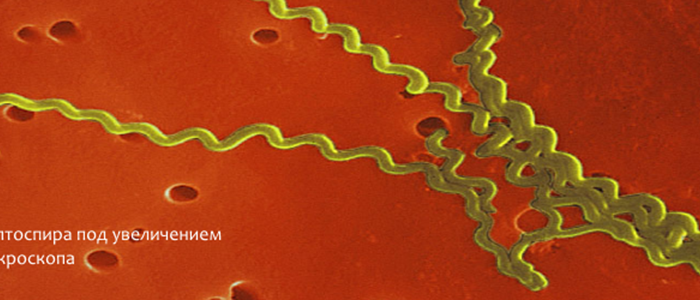

Лептоспиры: фотографии удивительных микроорганизмов